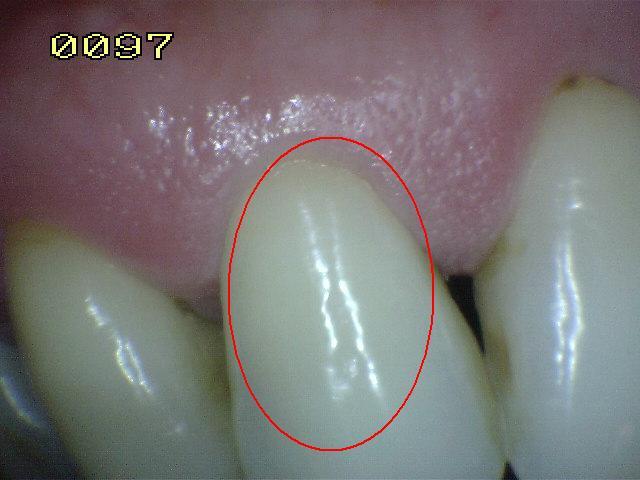

Código 1

(Caries Inicial): Primer cambio

visible en el esmalte seco